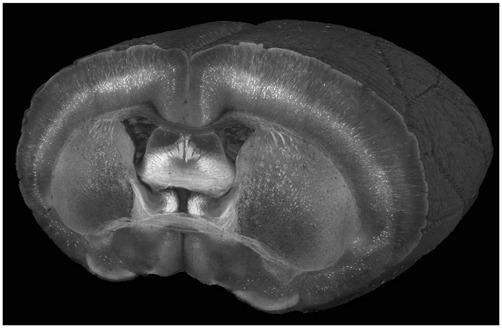

Whole Brain Imaging with Serial Two-Photon Tomography.

Imaging entire mouse brains at submicron resolution has historically been a challenging undertaking and largely confined to the province of dedicated atlasing initiatives. This has limited systematic investigations into important areas of neuroscience, such as neural circuits, brain mapping and neurodegeneration. In this article, we describe in detail Serial Two-Photon (STP) tomography, a robust, reliable method for imaging entire brains with histological detail. We provide examples of how the basic methodology can be extended to other imaging modalities, such as Optical Coherence Tomography (OCT), in order to provide unique contrast mechanisms. Furthermore, we provide a survey of the research that STP tomography has enabled in the field of neuroscience, provide examples of how this technology enables quantitative whole brain studies, and discuss the current limitations of STP tomography-based approaches.